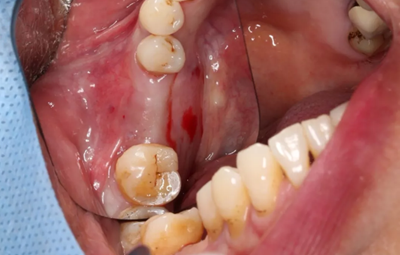

13、術(shù)后4個(gè)月復(fù)查、植骨

4月后二期手術(shù)前口內(nèi)情況

(攝于2017年8月10日)

翻瓣,發(fā)現(xiàn)種植體唇側(cè)骨壁吸收至根部。

遠(yuǎn)中骨壁部分吸收,近中及舌側(cè)骨壁完整,種植體無松動(dòng)。